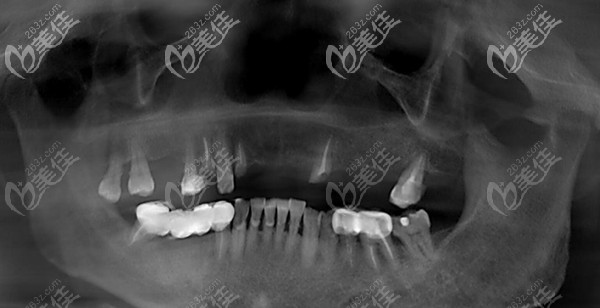

64歲阿姨口內(nèi)檢查:多顆牙缺失,深覆合深覆蓋,12、14、22殘根,牙體變紅,13、15、17、27 II-III°松動,余牙缺失。

診斷結(jié)果:牙列缺損,牙周炎,牙體缺損

治療方案:拔除上頜余牙,allon6即刻負重種植修復

王阿姨來到南京貝芽口腔,在護士的陪伴下,測量體溫表登記,隨后做了全景CT檢查獲取口腔數(shù)據(jù)。